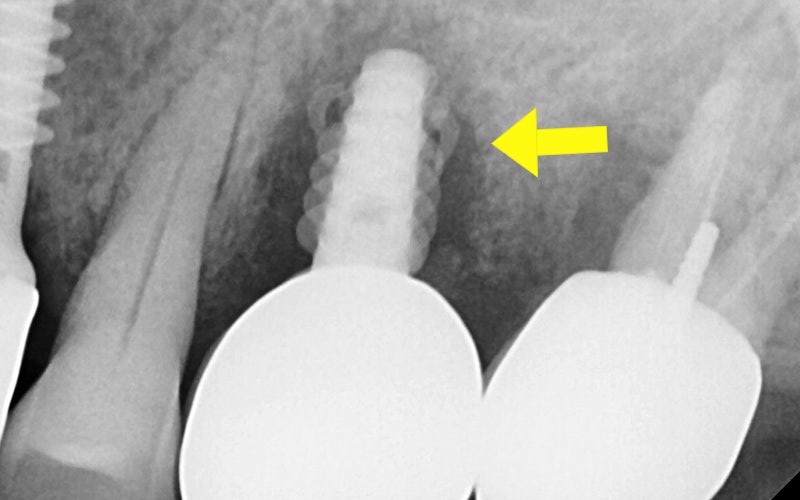

🔷 임플란트가 부러졌던 환자분 이야기

2025.06.03

“심은 지 3년도 안 됐는데

임플란트가 부러졌어요…”

위 환자분께서는

타 치과에서 임플란트를 심은 지

약 3년밖에 되지 않았다고 하셨는데요.

임플란트가 물리적으로

파절(나사체 부러짐) 되었고,

잇몸 염증까지 발생해

주변 치아까지 영향을 주는 심각한 상황이었습니다.

위 사진은 실제로 제거한 임플란트인데요.

나사체가 금속 피로로 인해 뚝 부러졌고,

머리 부분 근처에는 치석과 염증이

가득한것을 확인할 수 있습니다.

주변 잇몸뼈가 녹아내려

결국 옆 치아까지 발치 하였고

결국 임플란트를 다시 심어야 했고,

전체적인 재건이 필요했습니다.